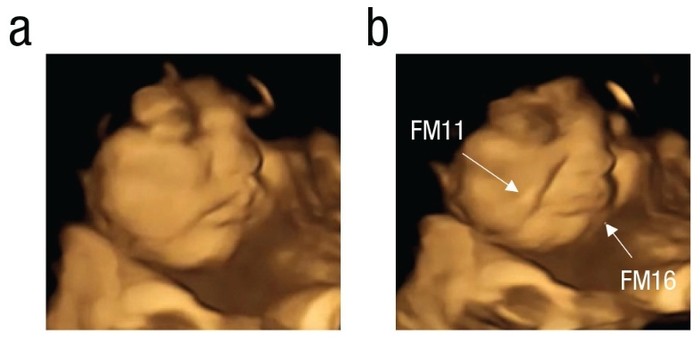

| ▲ 케일에 노출된 태아의 우는 얼굴 모습의 예: (a) 기준선, (b) 우는 얼굴 모습(정점). FM11 = 팔자 고랑; FM16 = 아랫입술 누르기. (출처: Flavor Sensing in Utero and Emerging Discriminative Behaviors in the Human Fetus / Psychological Science / First published online September 21, 2022) |

엄마가 단 당근 가루를 삼키자 아이들은 입을 크게 벌리고 웃는 듯한 표정을 짓거나, 입술을 오므리는 빨기를 빨았다. 케일의 쓴 향과는 다르다. 태어나지 않은 아이들은 입술을 맞대거나 윗입술을 들어 반응했다. 그들의 표정은 팀이 설명하는 것처럼 갓 태어난 아기의 방어적인 표정과 비슷했다. Ustun은 "당근이나 케일 맛에 대한 아이들의 반응을 보고 이 순간을 엄마와 함께 나누는 것은 정말 놀라운 일이었다"고 말했다.